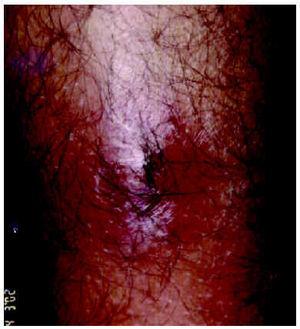

A la exploración se observaban cinco lesiones nodulares inflamatorias, con una zona blanquecina central y discreto edema periférico, localizadas en ambas piernas (fig. 1). No se palpaban adenopatías. Se efectuó expresión mecánica de una de las lesiones obteniendo una larva viva de aproximadamente 1 cm de longitud. Con la ayuda de una pinzas de disección, se extrajeron larvas similares de cada una de las otras lesiones (fig. 2). La larva fue identificada como Cordylobia antropophaga por sus características morfológicas y por su procedencia, y se recomendó tan sólo limpieza de las lesiones con un antiséptico, obteniéndose la resolución de aquéllas en pocos días.

Fig. 2.--Aspecto de la larva.